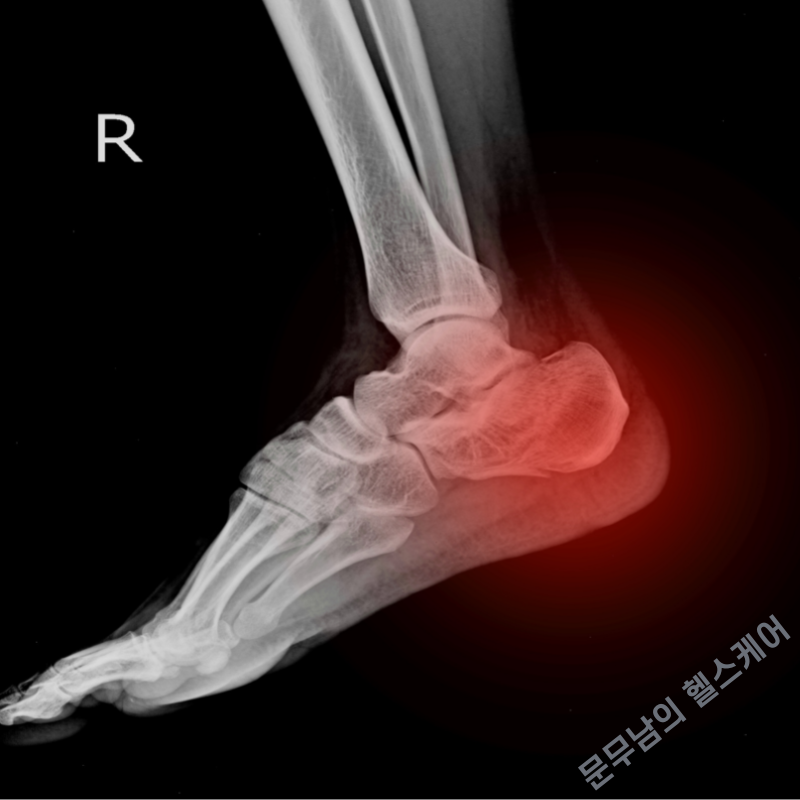

발뒤꿈치뼈 피로골절이란, 발뒤꿈치를 구성하는 뼈인 종골에 작은 균열이나 미세한 골절이 생기는 것을 의미합니다. 즉 반복적이고 과도한 스트레스로 인해 뼈에 미세한 실금이 가는 것이라고 볼 수도 있습니다. 피로골절과 미세골절은 둘 다 같은 용어에 해당합니다.

발뒤꿈치뼈 피로골절은 주로 맨 발로 달리기를 하거나, 줄넘기를 하는 경우 자주 발생하는 질환으로 경우에 따라 '신스프린트'라고 하는 정강이뼈 미세골절과 동시다발적으로 발생하는 경우도 있습니다. 지금부터 해당 질환의 주요 원인과 증상 및 치료법에 대하여 자세히 알아보도록 하겠습니다.